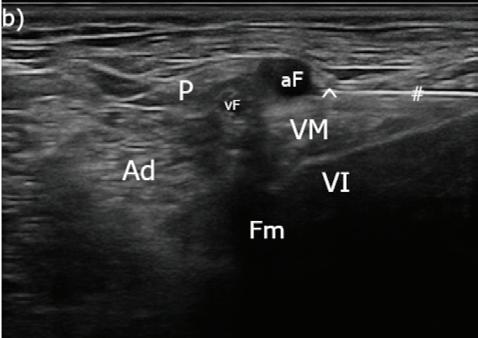

Tras rasurar y desinfectar la EPD, se realizó un bloqueo ecoguiado de los nervios ciático (Fig. 3A) y safeno (Fig. 3B) en el fémur medio,6 con bupivacaína 0,5 % (Bupivacaina 5 mg/ml, B Braun, Rubí (Barcelona), España; 0,1 ml/kg/nervio) y dexmedetomidina (1 μg/kg/nervio). Para ello se utilizó una sonda lineal multifrecuencia 3-13 MHz (MyLab Gamma, Esaote, Florencia, Italia) y agujas sonovisibles (Ultraplex® 360 x 10 mm, 30º, BBraun, Melsungen, Alemania).

Figura 2. Ecocardiografía. (A) Vista apical izquierda de 4 cámaras optimizada para ADD. Engrosamiento de la válvula mitral (VM), dilatación moderada de atrio izquierdo (AI) y ventrículo izquierdo (VI). Estructura redondeada y anecógena de 15 mm con flujo sanguíneo (AAD), adyacente al corazón. AD: atrio derecho. (B) Vista paraesternal derecha de 4 cámaras optimizada para el atrio izquierdo. Estructura redondeada y anecógena (AAD) asociada al corazón. AD: atrio derecho.